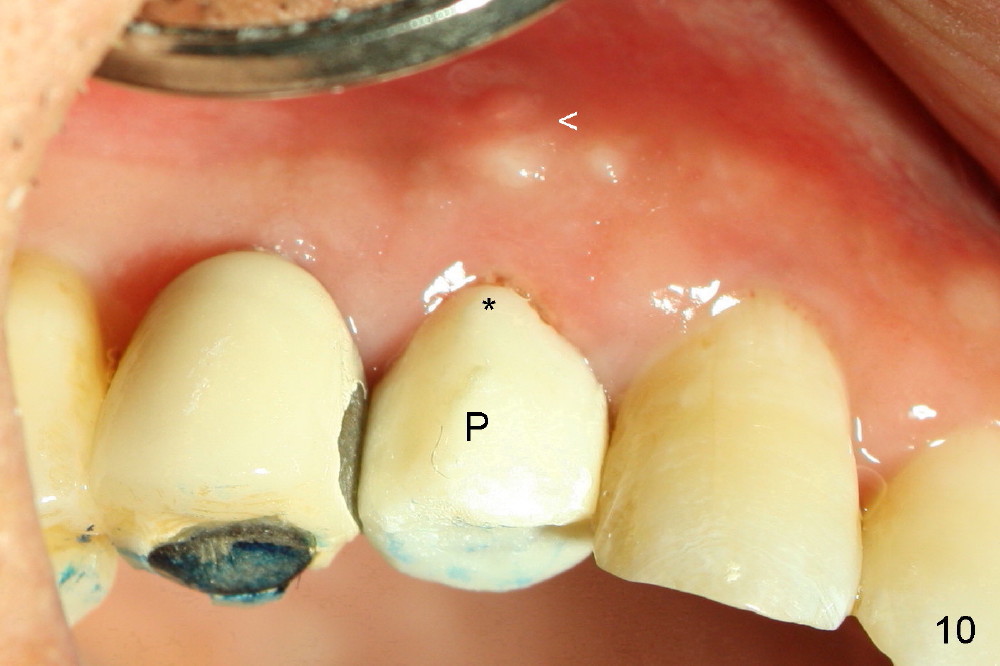

A 57-year-old man refuses treatment for the tooth #5 for 22 months (Fig.1). He suddenly shows up because of severe bleeding from the fistula of the tooth (Fig.2 <). After lengthened discussion, he agrees extraction (Fig.4) and immediate implant (Fig.5-8).

As expected, the collagen dressing is dislodged when the perio dressing is off; fortunately the bone graft remains in place 7 days postop (Fig.9 *). To keep the bone graft in place, an immediate provisional (Fig.10 P) is fabricated and cemented; its margin (*) covers the graft. There is no occlusal contact in centric and lateral excursion. The patient is asked not to use this crown for 3 months.